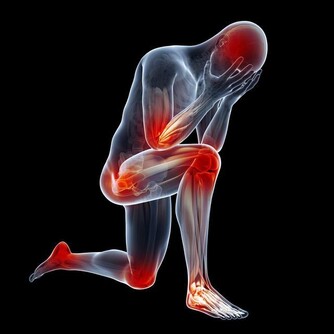

痛風石中老年人比較常見的疾病之一,男性患者比較多,往往夜間突然發病,局部關節紅腫、疼痛劇烈,皮膚會呈青紫色、發亮,有明顯的壓痛感以及局部隆起現象,有時關節還會有活動障礙現象的發生。